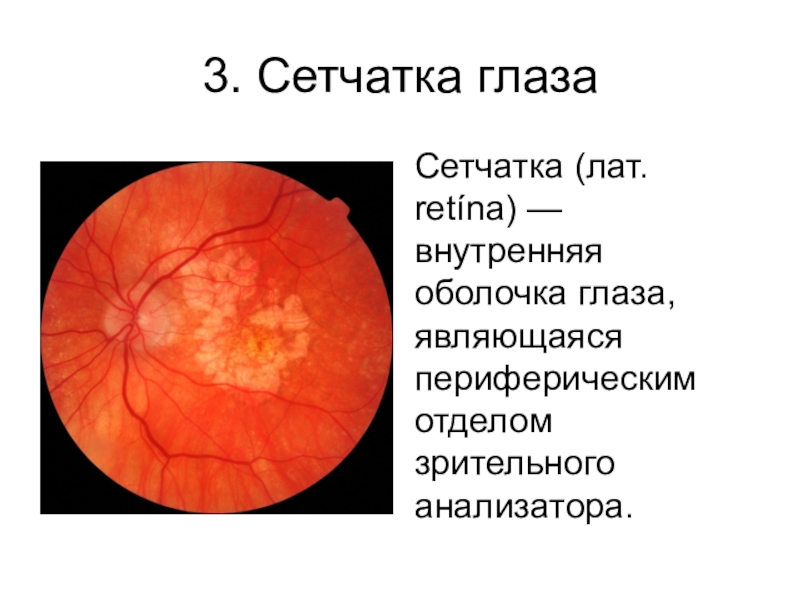

Изображения и анатомия сетчатки глаза

Раздел: Визуальный дайджест